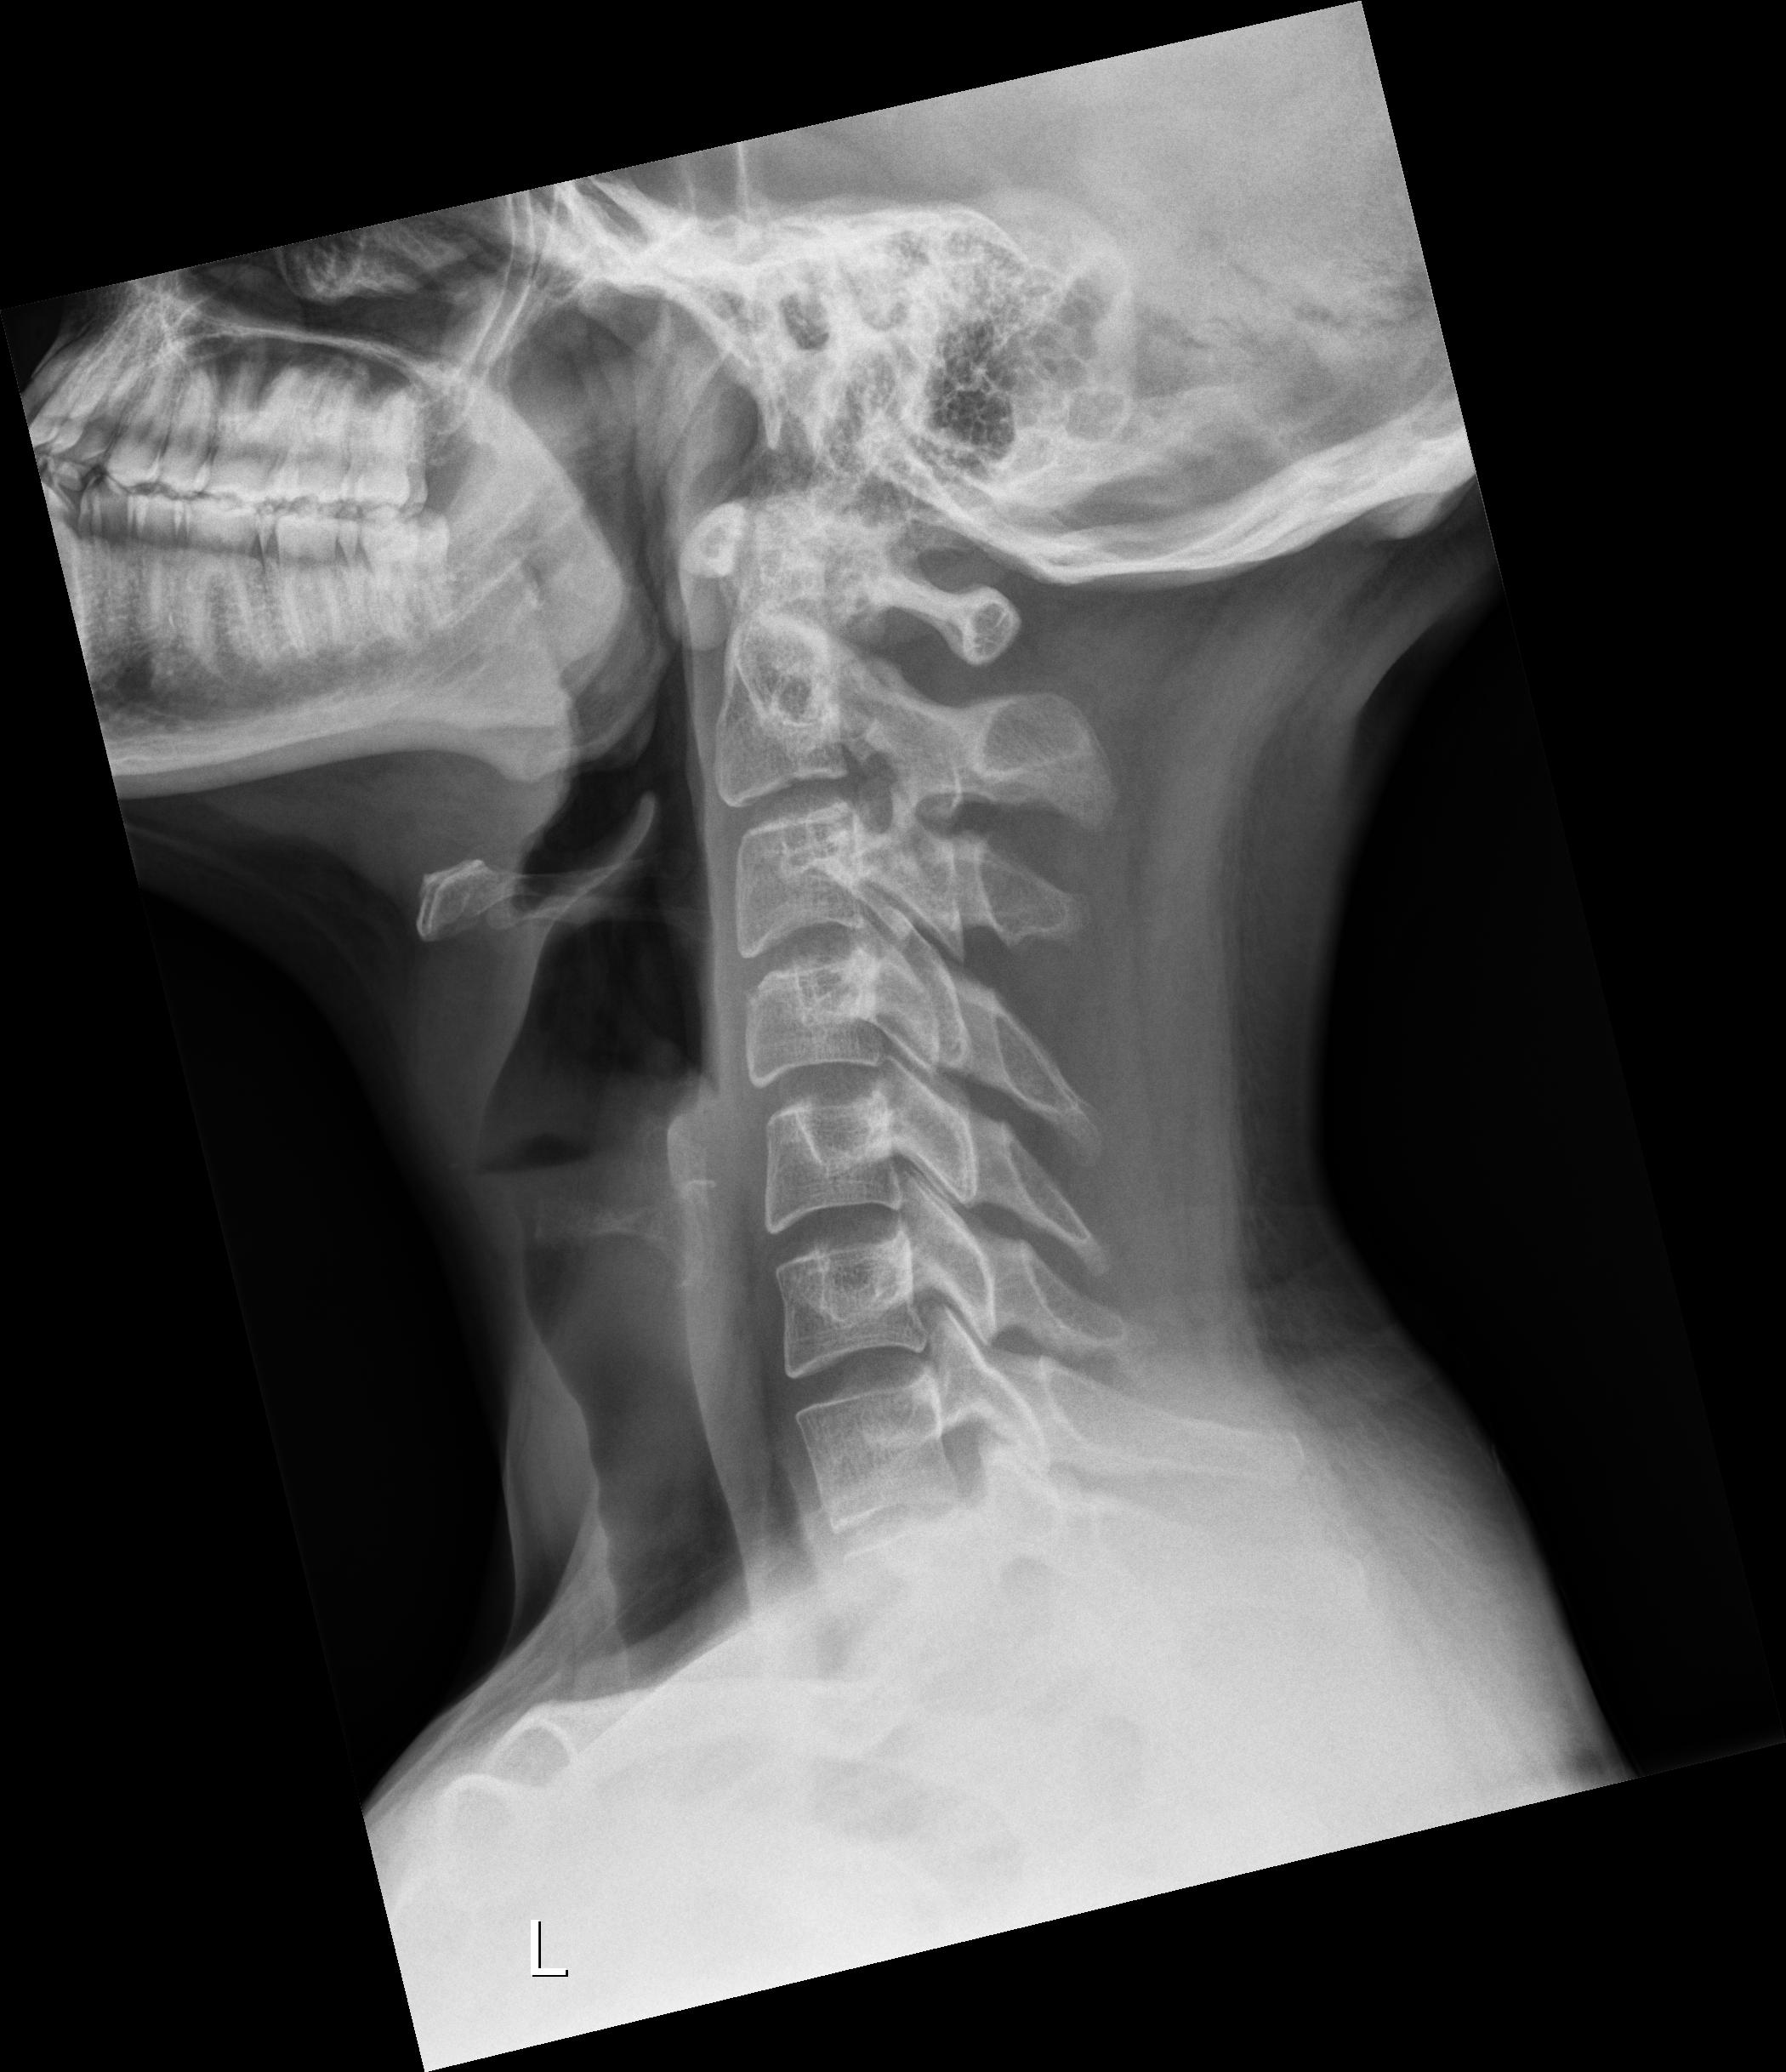

A few days ago, I started having swallowing difficulties. When I reached to the back of my mouth with my finger, I was shocked to feel a bony structure instead of the normal soft tissue. Since it was late and I had little access to my GP, I used ChatGPT, which suggested it might be Eagle syndrome. I then did some research and found your group.

What worries me is that my oxygen supply to the brain may have been limited for so long that it caused structural neural damage. I will ask my GP and push hard for a CT scan of my neck. But I want to ask you: have any of you had similar issues, and after the operation, did your symptoms—even if severe initially—resolve completely, especially cognitive ones?